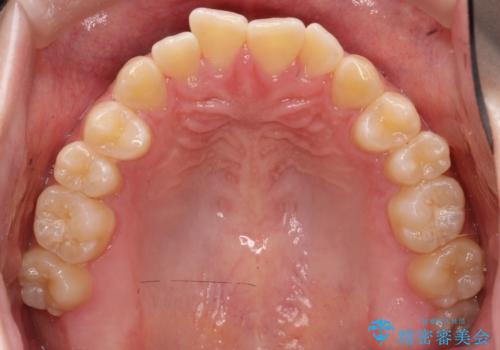

【インビザライン】オープンバイト。凸凹を治したい

- オープンバイトを主訴に来院されました。

インビザラインを用いIPRと遠心移動を行いオープンバイトと叢生の改善を行なっております。

前歯の叢生がわずかにありますが、追加アライナーの作成は希望されなかったため、歯を動かしていく動的治療は終了となりました。